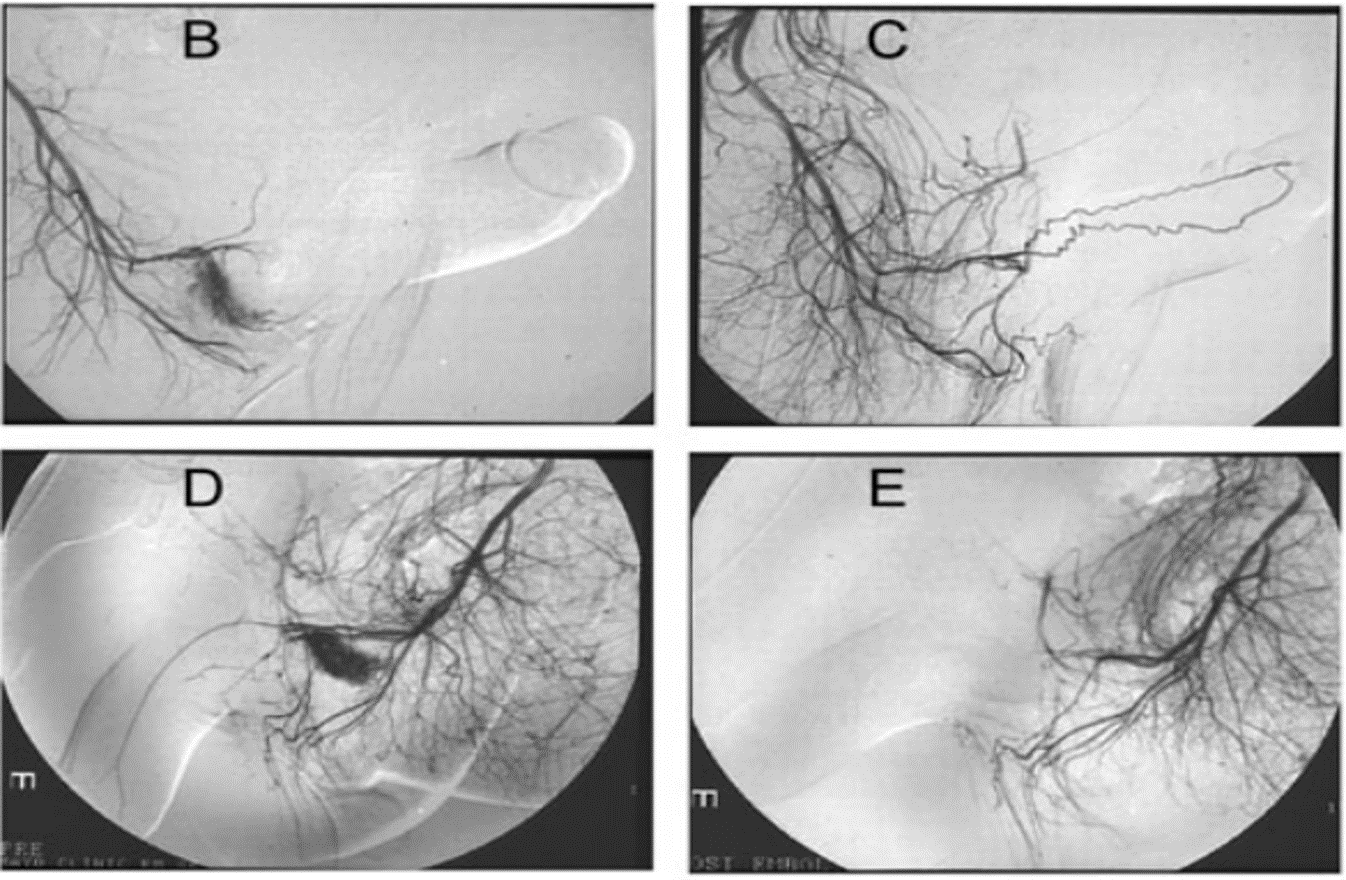

Nút mạch chọn lọc

Nút động mạch chọn lọc có thể sử dụng cục máu đông tự thân, gel bọt hoặc bọt biển, hoặc các chất bền vững hơn như coil hoặc keo acrylic. Tỷ lệ thành công lên tới 89%.

Về mặt lý thuyết, việc dùng cục máu đông tự thân có nhiều ưu thế hơn những vật liệu khác, vì cục máu đông tạm thời hàn lại lỗ rò, cho đến khi khối máu tụ bị ly giải, tổn thương động mạch thể hang có thể đã lành. Việc sử dụng các vật liệu bền vững, sẽ chặn vĩnh viễn động mạch và có thể dẫn tới tác dụng không mong muốn liên quan tới rối loạn chức năng tình dục sau này (chủ yếu là rối loạn cương dương). Các tác dụng không mong muốn khác bao gồm hoại thư dương vật, thiếu máu vùng mông, viêm vật hang và áp xe đáy chậu.

Sau nút mạch qua da, tiếp tục theo dõi trong 1 đến 2 tuần. Xác định việc nút mạch thành công hay không có thể dựa trên khám lâm sàng và bằng siêm âm Doppler màu. Nếu có nghi ngờ, việc chụp mạch lại được yêu cầu. Tỷ lệ tái phát từ 30 - 40% sau nút mạch đơn thuần. Kỹ thuật nút mạch tạm thời có chọn lọc có thể bảo tồn được chức năng cương ở 90% người bệnh cương đau dương vật kéo dài thể không thiếu máu.

Nút mạch chọn lọc điều trị cương đau dương vật kéo dài thể không thiếu máu